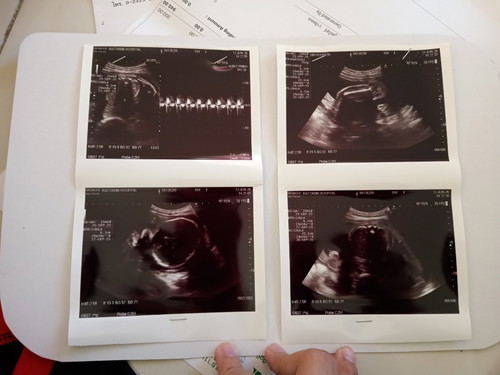

แอบดูเด็กน้อย

วันนี้ไปตรวจเด็กน้อยมาก ทำเอาแม่ปวดร้าวไปหมด อยู่ๆน้องกลับด้านหันหลังออกด้านนอก แม่ก็ใจเสียไม่รู้สึกว่าลูกดิ้นเลย นอนกลับหัวหันขาขึ้นมาอีก ปกติดิ้นเก่งดิ้นแรง หืมมม..จิงๆเลย 26w2d #น้องนอนกลับหัวจำเป็นต้องคลอดมั้ยคะ รึปกติ #ท้องแรกคะ #ถีบทีจุกที??

แม่น้องออมสิน